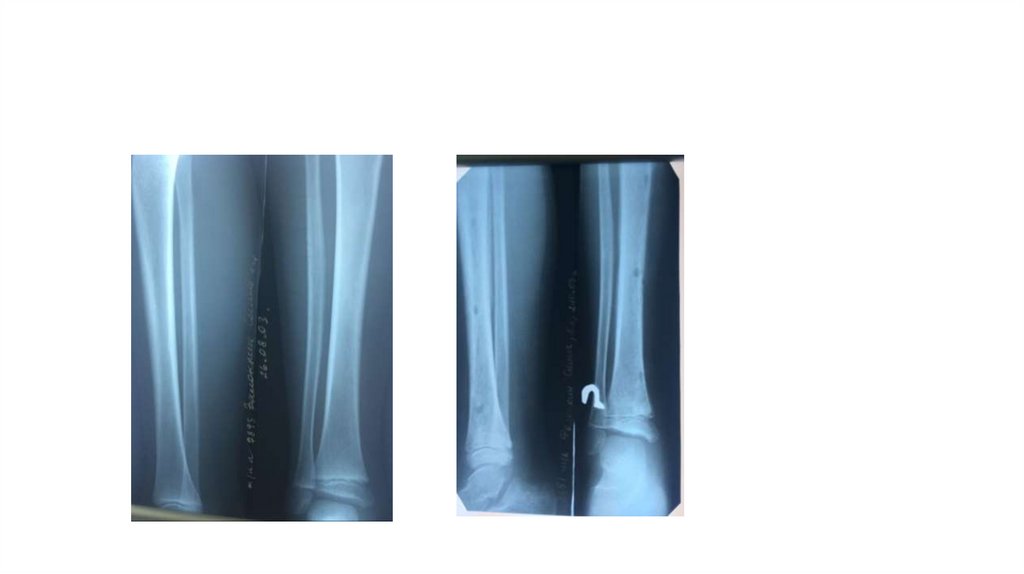

Воспалительные заболевания опорнодвигательного аппарата

«Воспалительные

заболевания опорнодвигательного аппарата»